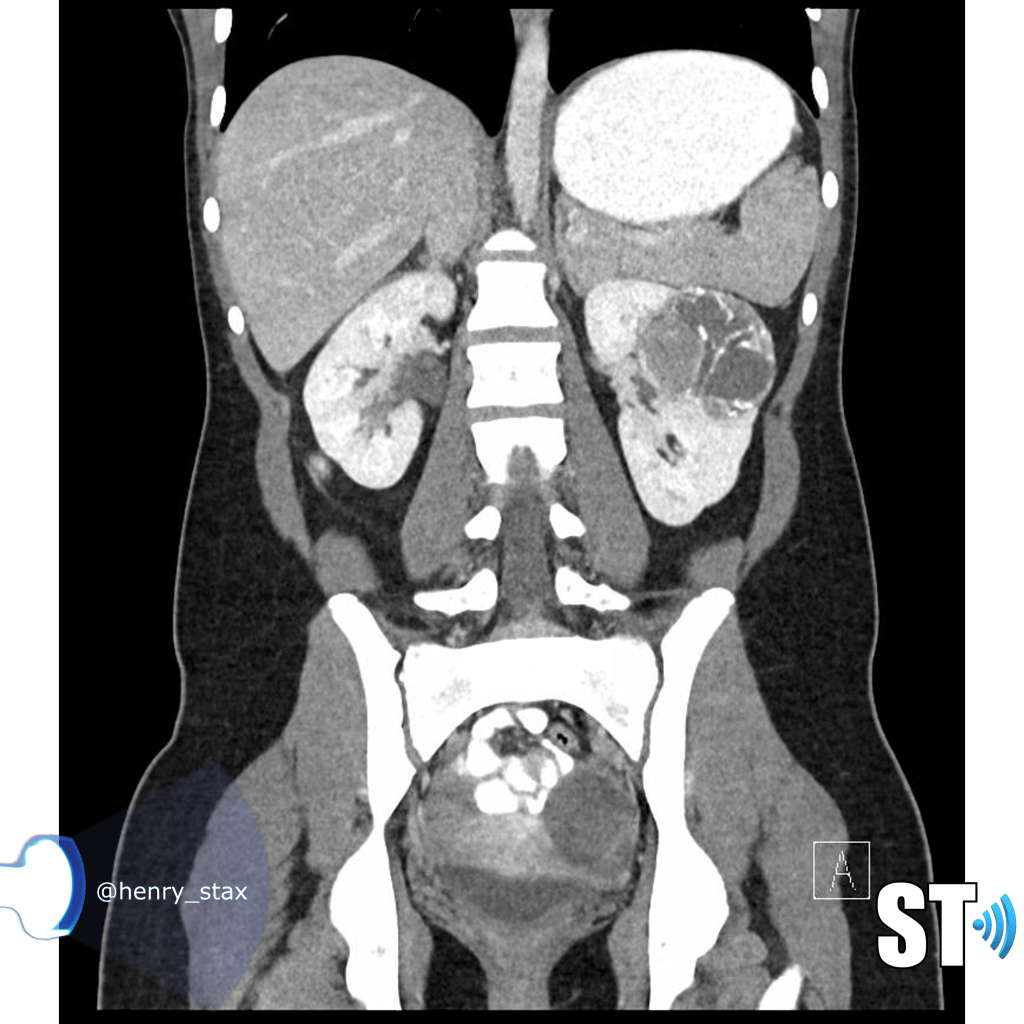

ARPKD

Autosomal Recessive Polycystic Kidney Disease (ARPKD) Typically presents around birth, though it can present later in childhood. Cases that develop later have a propensity to be associated with hepatic fibrosis. ARPKD is transmitted in an autosomal recessive pattern meaning two copies of an abnormal gene must be present in order for the disease or trait to develop.

- Infantile

- Kidney enlargement (sometimes massive)

- >80% liver cysts

- Multiple organs affected

- Hyperechoic